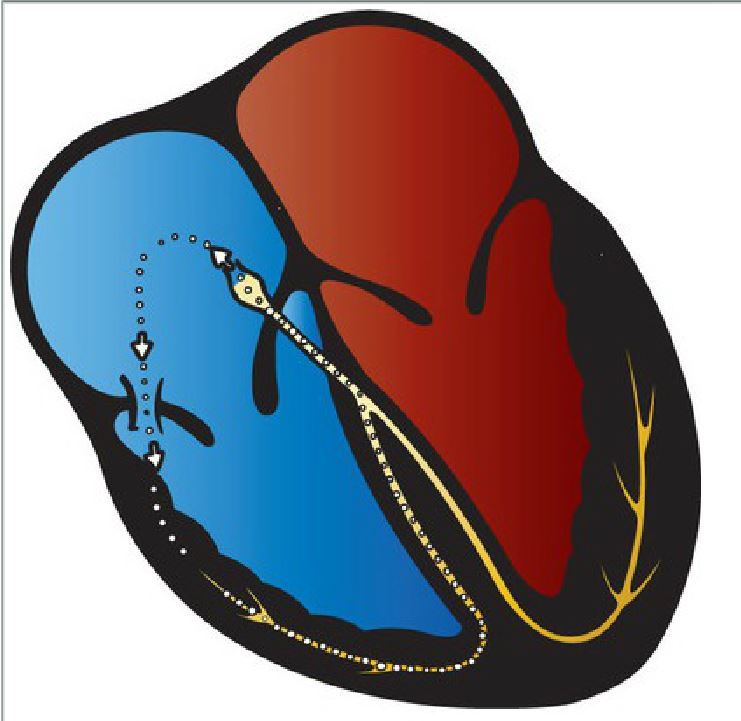

PSVT in WPW syndrome with antegrade reentry loop. Current moves antegrade down the bundle of Kent and then retrograde through the AV node, establishing an independent revolving circuit. The ventricles are activated through the accessory pathway, generating wide QRS. It’s also called antidromic tachycardia

A Fib in WPW. The bundle of Kent can act as a free conduit for chaotic atrial activity, W/o the AV node to act as a barrier, the ventricular rates can rise as high as 300bpm, which can induce V Fib.